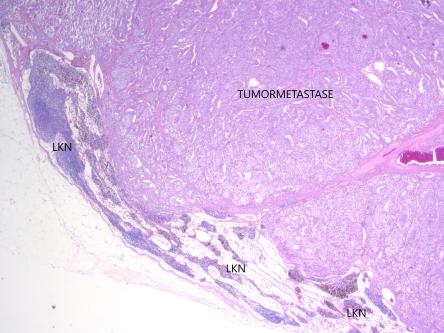

Vorerst erhält Nico Medikamente, welche den Blutzucker stabilisieren sollten; leider zeigt der Hund aber weiterhin Kollapse aufgrund von Unterzuckerungen. Die Besitzer möchten nichts unversucht lassen, weshalb wir Nico an eine onkochirurgische Spezialistin überweisen. In einer grossen Operation wird der befallene Teil der Bauchspeicheldrüse, der veränderte Lymphknoten, die ebenfalls veränderte Milz sowie zwei Leberlappen entfernt. Anschliessend erhält Nico einen Freestyle-Libre-Sensor aufgeklebt (siehe Fall des Monats Februar), damit die Besitzer den Glucosespiegel überwachen können. Das entfernte Gewebe wird durch einen Pathologen untersucht. Die Gewebeuntersuchung bestätigt, dass es sich bei der Bauchspeicheldrüsenmasse um ein Insulinom handelt, welches in einen Lymphknoten metastasiert hat. Die Veränderungen der Milz sind gutartig; bei den entfernten Leberknoten handelt es sich nicht um Insulinom-Ableger, sondern um primäre Lebertumoren.

Wir danken Dr. N. Kühn herzlich für die Zurverfügungstellung der histologischen Aufnahmen.